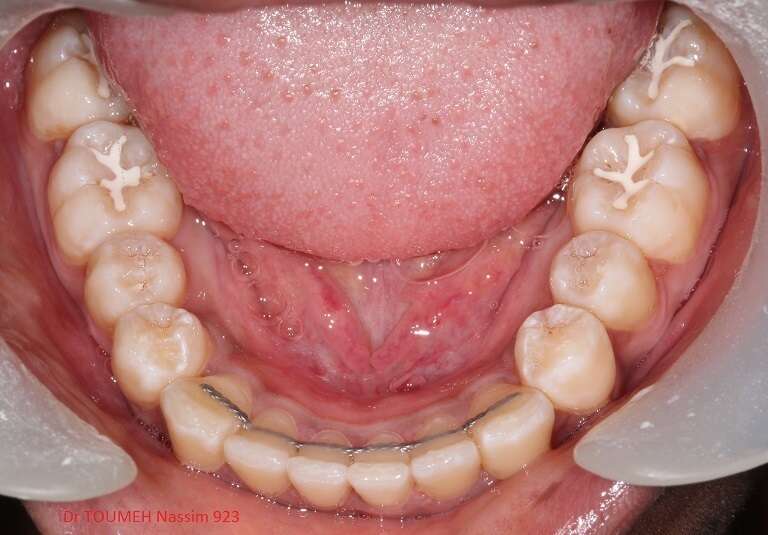

Latérales naines et orthodontie

la forme des dents influence grandement l’esthétique du sourire

La malformation des incisives latérales en est l'illustration

Le traitement consiste à redresser les dents à l'aide d'un appareil orthodontique (Multiattaches) et à redonner une forme normale aux dents malformées.

Dans ce cas présenté des couronnes provisoires en résines ont été posées.

Après